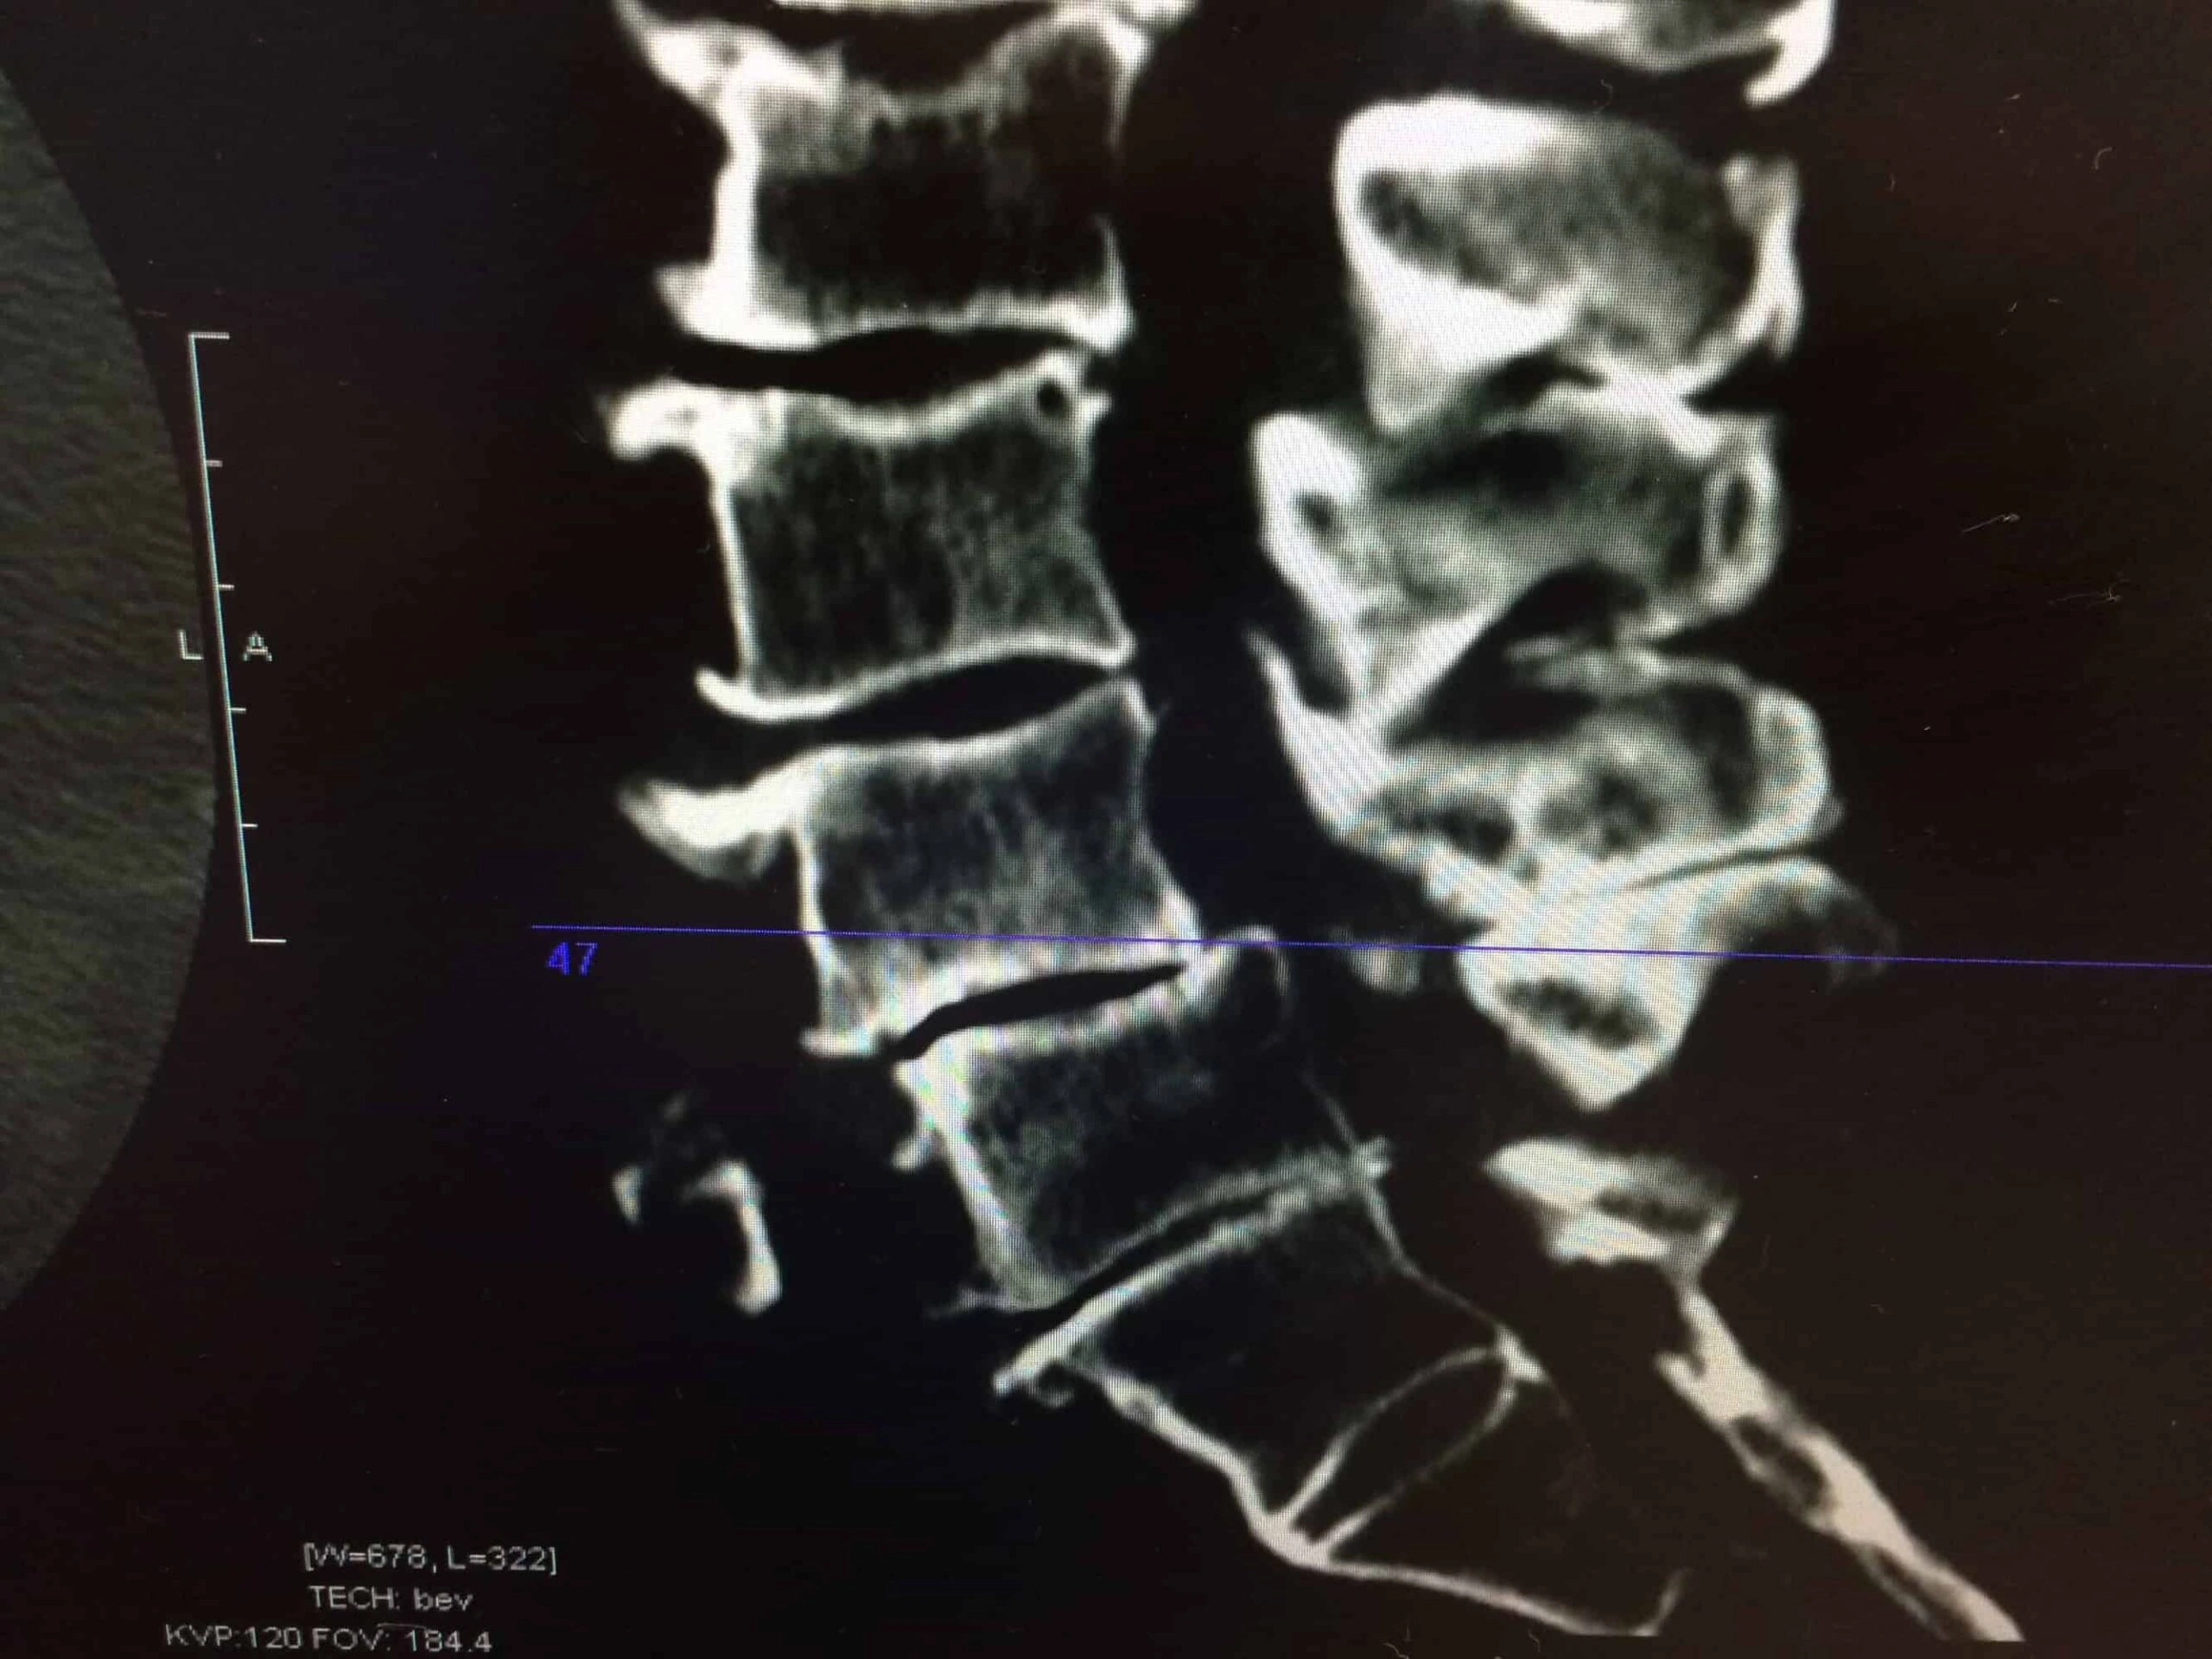

Spondylolisthesis happens when one vertebra slips out over the one below it. When this does cause symptoms, they are usually back and leg pain. Some severe cases can cause other, more serious issues. Regardless of whether your spondylolisthesis is causing you pain, it’s important to seek proper conservative care from a trusted Anchorage, Alaska chiropractic doctor or other medical professional.

An old study posted on Europe PMC involving 47 patients showed that flexion-based exercises (gentle bending) were more effective than extension-based exercises (backward bending). Patients who did flexion exercises had better outcomes, such as returning to work without modifications and less need for a back brace.